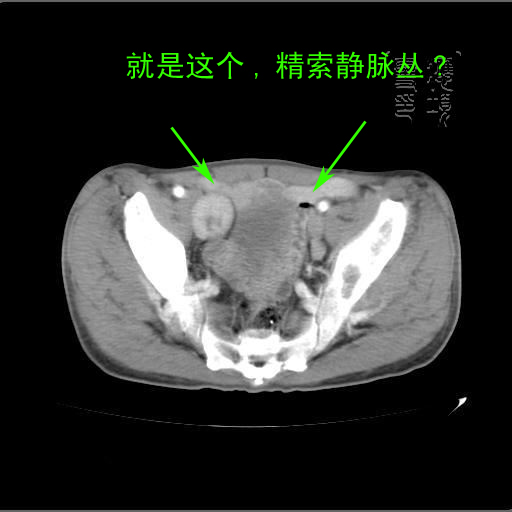

以下是引用余辉在2007-4-20 20:03:00的发言:[br]没头绪,猜一个吧,距离血管鞘近,就猜神经鞘瘤,中心部分变性囊变,另外请哪能位老师指点腹直肌后方及后外方强化物是何

以下是引用dyqct在2007-4-20 20:51:00的发言:[br]考虑:1、右侧膀胱外上方实性富血管性肿瘤(神经鞘膜瘤?纤维瘤?巨淋巴结增生症?)[br] 2、请标识需要解释的地方。

以下是引用aa13877358820在2007-4-21 7:01:00的发言:[br]隐睾?